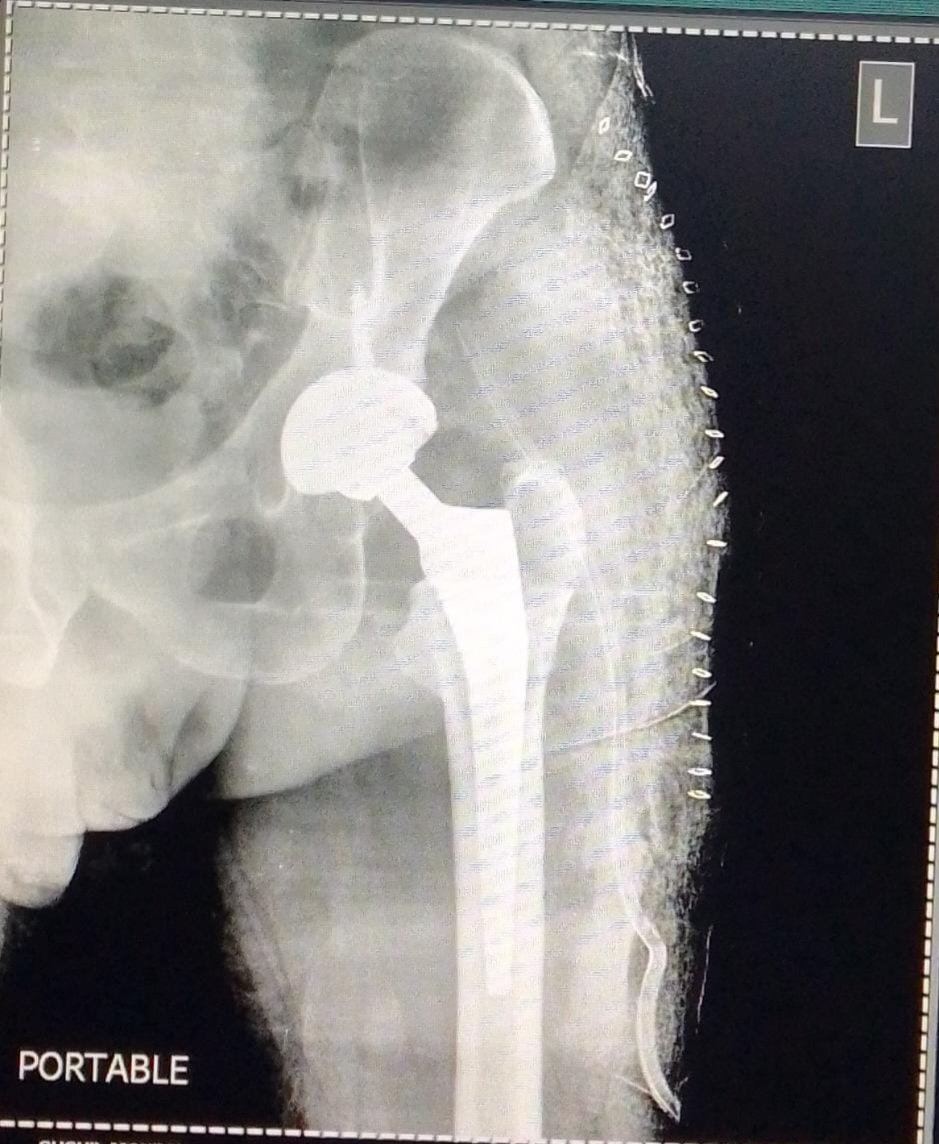

Post-Op X-Ray

Revision Long Stem THR in Aseptic Loosening of Fixed Bipolar Prosthesis

DHS Failure & Long Stem THR